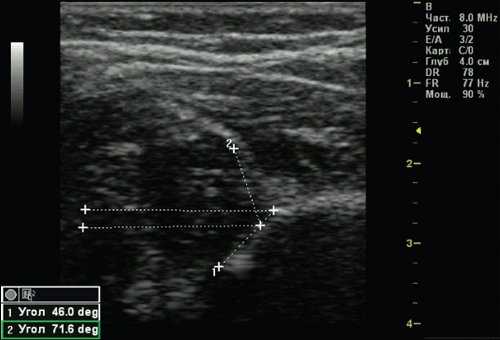

Тип 2с тазобедренных суставов (рис. 5) обнаружен у 2 (0,51%) детей. Это вариант тяжелой дисплазии в любом возрасте. Все составляющие сустава недоразвиты. Костная часть вертлужной впадины уплощена, костный эркер закруглен или плоский, хрящевая часть вертлужной впадины расширена, но еще охватывает головку бедра. Угол α меньше 49°, но больше 43°, угол β больше 65°, но меньше 72°. Такой тип суставов без соответствующего лечения, влечет прогрессирующее децентрирование головки бедра.

Рис. 5. Тазобедренный сустав тип 2с.

1 - угол α=46,0°;

2 - угол β=71,6°.